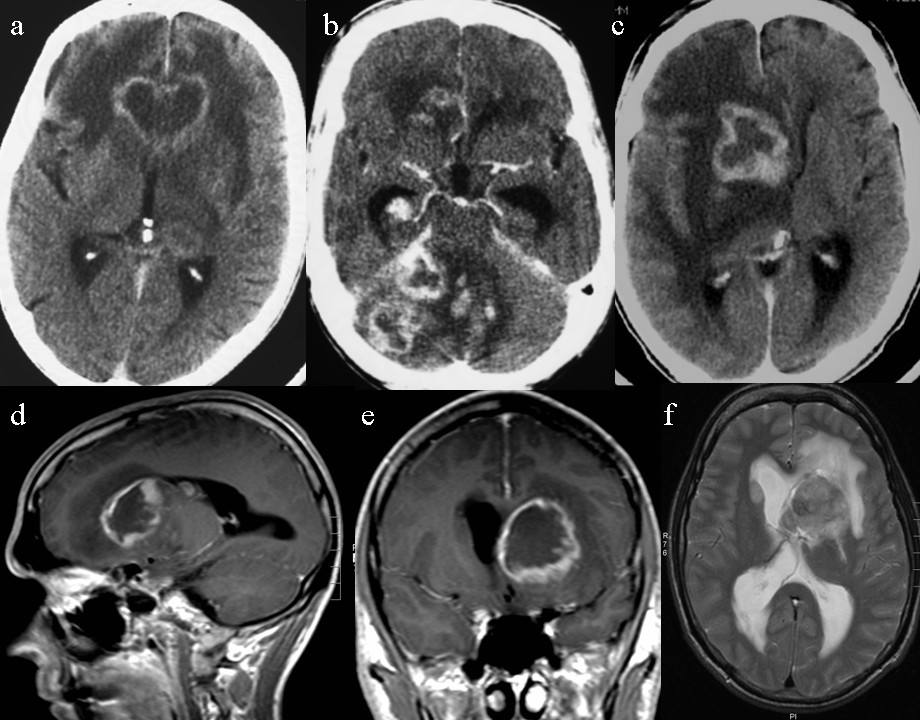

Review of CT/MRI in 14 patients revealed no brain lesion in 1 (7%), a single lesion in 2 (14%), and multiple (2–7) lesions in 11 (79%) patients. In the patient with no lesion, CT one week prior to death indicated hydrocephalus. All together, 37 lesions (36 at CT and 9 at MRI) were identified; involving the lobes in 11 patients (79%) and the deep structures of the brain in 8 patients (57%) (Table 1). All lesions enhanced after intravenous contrast injection; 75% showed ring-enhancement both at CT (27/36) and MRI (6/8) (Figure 2).

Figure 2

AIDS-related PCNSL in Norway: imaging findings at CT and MRI. Contrast enhanced CT in 3 patients demonstrating lesions with ring-enhancement in the frontal lobes (a), cerebellum (b) and basal ganglia (c). MRI (d-f) in another patient with lesion in the basal ganglia at T1 (d-e) and T2 (f) weighted images.